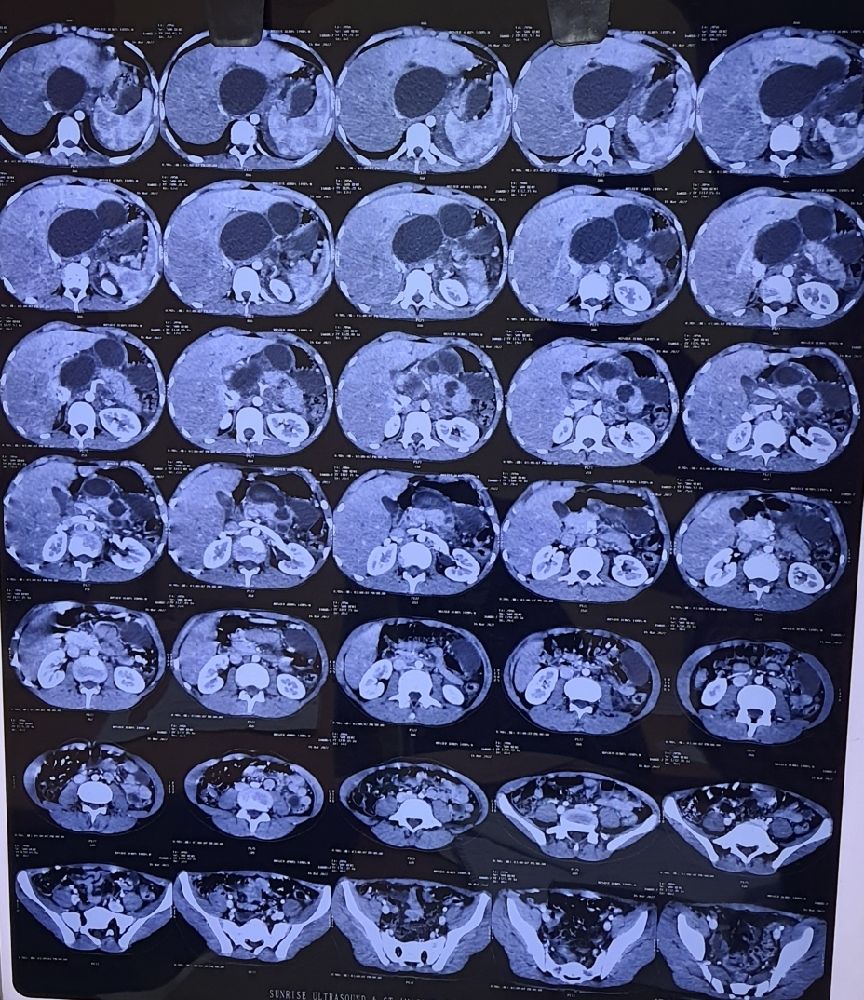

From www.researchgate.net

35 years male presented with left lower abdominal pain and fever and Male Lump Stomach Learn about the causes, symptoms, diagnosis, and treatment of a mass in the stomach. An abdominal mass is any abnormal growth that occurs within the abdomen. There are various causes of these masses, including. An abdominal mass is a growth or swelling in a part of your abdomen. One of the most common causes is a hernia, but other causes. Male Lump Stomach.